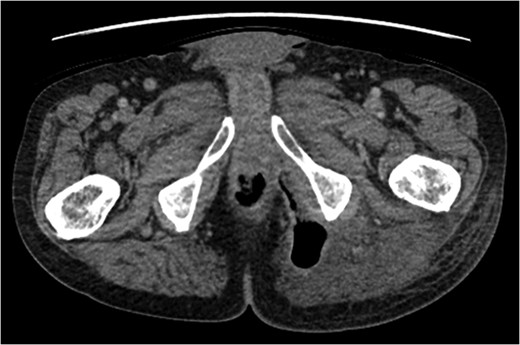

A rare complication of diverticular disease is the formation of fistulas, most commonly either colo-vesical or colo-vaginal. We present the unusual case of a perforated sigmoid diverticulum forming a colo-gluteal fistula and presenting initially as a gluteal abscess in an otherwise asymptomatic patient. After drainage of the gluteal abscess, the patient re-presented with faecal loss from the abscess drainage site. Imaging revealed fistulous communication between the sigmoid and the left obturator internus muscle, tracking to the gluteus maximus with associated abscess and cutaneous communication to the site of previous drainage. The patient underwent an emergency Hartmann's procedure with lay open/abscess drainage of the gluteal cavity. Post-operatively the patient experienced continuing discharge from the gluteal fistula despite repeated drainage and debridement causing considerable morbidity, inconvenience and misery. Clinicians should maintain a high index of suspicion when presented with a gluteal abscess and should consider the possibility of an intra-abdominal source.

An emergency Hartmann's procedure was performed under general anaesthetic through a lower midline incision as well as lay open of the perineal fistula. On opening the abdomen, a perforated diverticulum was identified extending into the left lateral pelvic wall. A standard Hartmann's procedure was performed, with sigmoid colectomy, division of rectum at recto-sigmoid junction and a tension-free stoma formed in left hypochondrium. The left buttock abscess cavity extended by a further 2–3 in. and the cavity then packed.